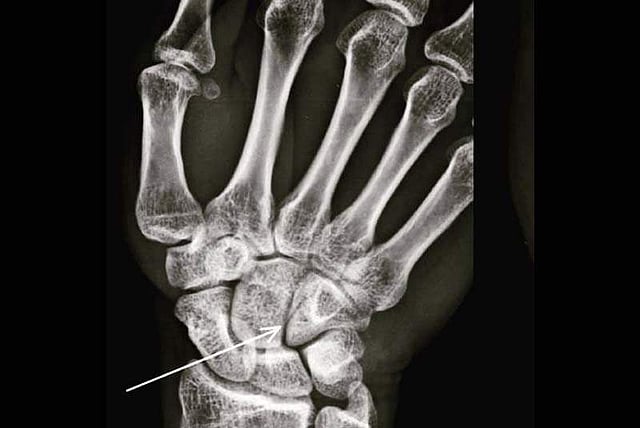

Farhan on Sunday shared a photograph of his X-Ray report on Instagram.

"When nature plays Tetris and yup, that's my first legit boxing injury... A hairline fracture on the hamate (courtesy @kongkoul ????) found among the carpal bones of the hand #nopainnogain #ToofanInTheMaking #trophycollector #weareallthesameinside," he captioned the image.